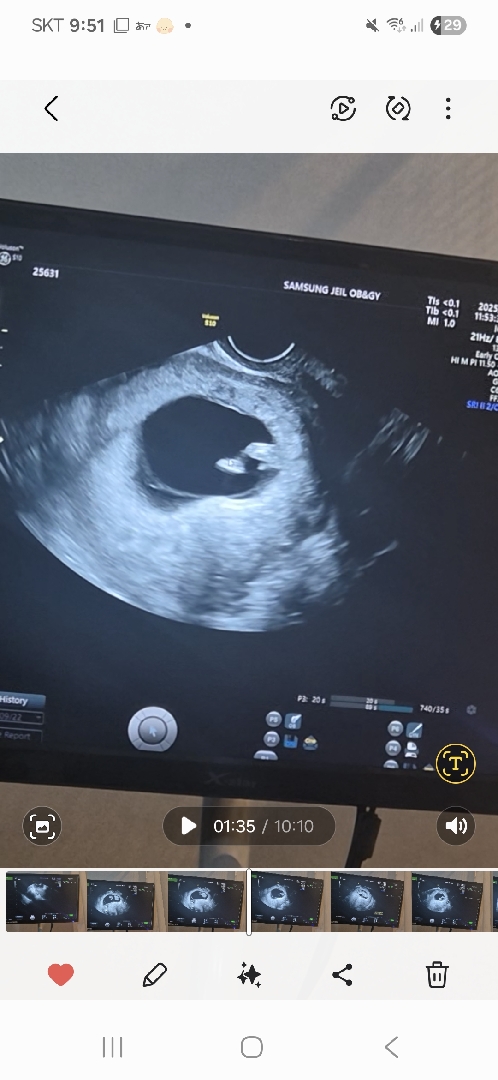

아들일까요?

아직 11주밖에 안됐는데 다리에 뭔가를 본거같아요

11주면 여아 남아 다 튀어나와있어서 몰라요! 각도법으로 추측만 해볼수있는듯해요ㅎㅎ